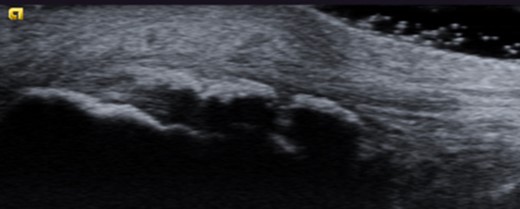

Dynamic ultrasound examination of the left heel showed a diffusely thickened subcutaneous bursa, with fluid-rich islands. Regions of high blood flow were seen in the bursal walls. There was tendinopathy in the distal Achilles, which measured 6–7 mm in thickness with intra-tendinous bone formations and calcification, but no high blood flow. Finally, there was a minor Haglund-like deformity with a sharp edge and a slightly enlarged retrocalcaneal bursa with the appearances of scar tissue formation, but no fluid or increased blood flow. There were no signs of partial ruptures in the distal part of the Achilles. These ultrasound findings were consistent with those of a previous MRI (Figs 1–5).

Ultrasound image of thickened subcutaneous bursa and bone formations in the distal Achilles.

Ultrasound image of diffusely thickened subcutaneous bursa and underlying intra-tendinous bone formations.